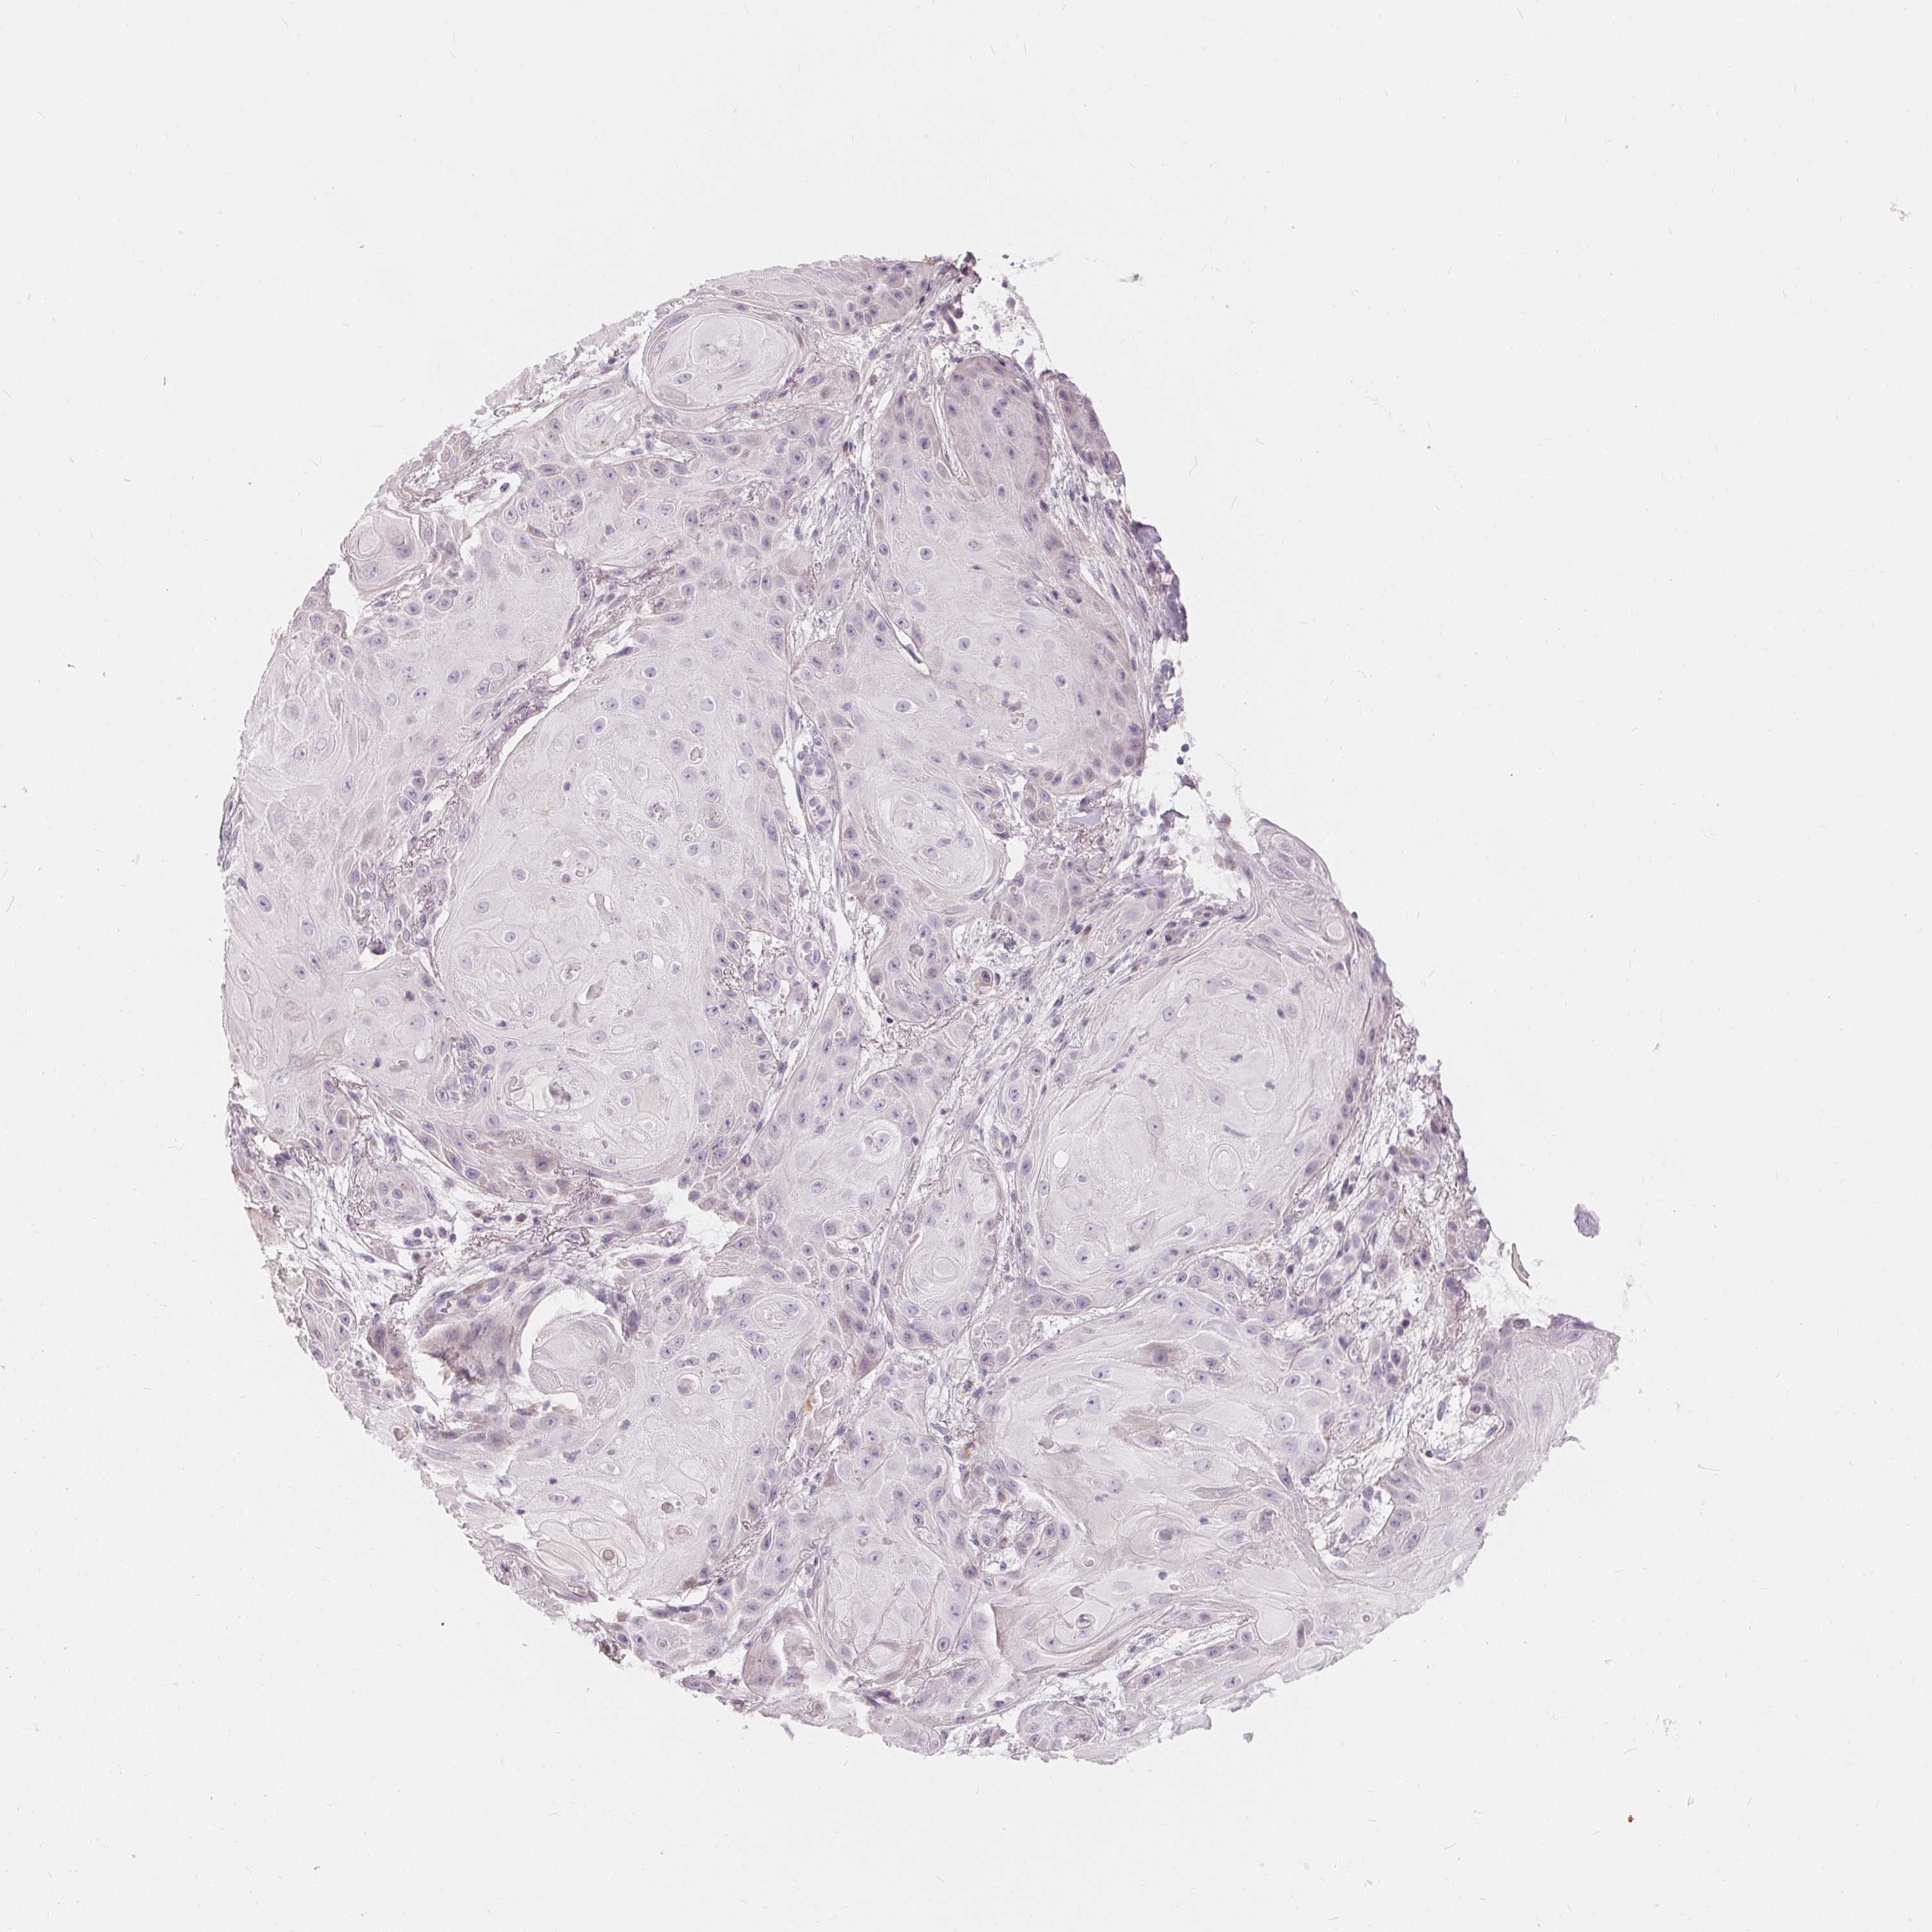

Basal cell and squamous cell cancer

SKIN CANCER - Protein expressioni

A mouse-over function shows sample information and annotation data. Click on an image to view it in a full screen mode. Samples can be filtered based on level of antibody staining by selecting one or several of the following categories: high, medium, low and not detected. The assay and annotation is described here.

Antibody stainingi

Antibody staining in the annotated cell types in the current human tissue is reported as not detected, low, medium, or high, based on conventional immunohistochemistry profiling in selected tissues. This score is based on the combination of the staining intensity and fraction of stained cells.

Each image is clickable and will lead to virtual microscopy that enables deeper exploration of all samples and also displays staining intensity scores, fraction scores and subcellular localization as well as patient and tissue information for each sample.

Antibody HPA030180

Antibody CAB018632

Staining

High

Medium

Low

Not detected

Intensity

Strong

Moderate

Weak

Negative

Quantity

>75%

75%-25%

<25%

None

Location

Nuclear

Cytoplasmic/membranous

Cytoplasmic/membranous,nuclear

Basal cell carcinoma

Squamous cell carcinoma, NOS